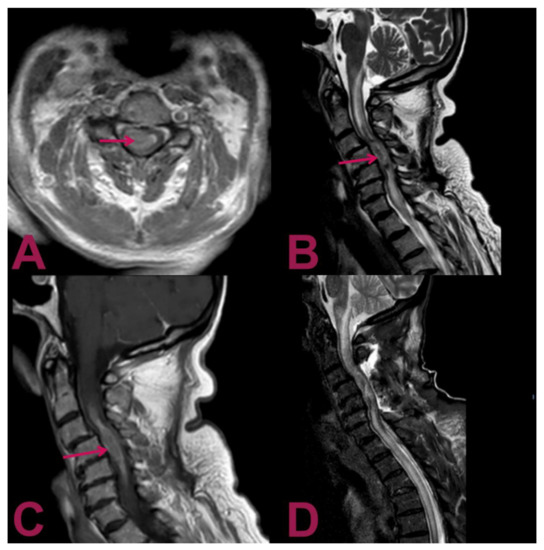

Magnetic resonance images (MRIs) of the cervical spine showed an intramedullary mass at the level of C2–C6 vertebrae, a heterogeneous hyperintense signal on the T2-weighted sequence, with a heterogeneous pattern of contrast enhancement that extended for about 6 cm associated with a syringomyelic cavity, from the bulbar–medullary junction to the D5 level inferiorly (Figure 1). Considering the correlation between these features and the patient’s history, the neuroradiologist made the diagnosis of anaplastic astrocytoma. The MRI of the brain and the preoperative chest X-ray were normal.

Figure 1. Magnetic resonance imaging (MRI) of the cervical spine. (A) Gadolinium-enhanced T1-weighted axial MRI shows an intra-axial lesion containing hemosiderin (arrow) with predominant right paramedian development. (B) T2-weighted sagittal MRI shows an extensive syringomyelic cavity, which covers the caudal portion of the floor of the IV ventricle and affects the posterior portion of the bulb–medullar junction extending up to the D5 level inferiorly. The syringomyelic cavity is the result of the newly formed tissue extending from C4 level for about 6 cm with a maximum diameter of about 15 mm (arrow). (C) Gadolinium-enhanced T1-weighted sagittal MRI displays the intramedullary mass at the C2–C6 level with a heterogeneous contrast enhancement pattern (arrow). (D) Postoperative T2-weighted sagittal MRI reveals the outcomes of hemilaminectomy C3–C4–C5 and cervical myelotomy with partial removal of the lesion; noticeably, despite the invasive nature of the surgical intervention, the previous parameters have not deteriorated; no worsening in the syringomyelic cavity is present, and the peri-wound oedema is not increased.

We reported a rare case of an intramedullary spinal cord metastasis, presented as the first manifestation of a lung small-cell neuroendocrine carcinoma. Additionally, this is the first case reported in the literature of solitary intramedullary metastasis of the cervical segment originating from lung cancer. As we noticed, based on the magnetic resonance imaging for an intramedullary infiltrating lesion, the diagnosis is likely compatible with an intramedullary astrocytoma. The lesion presented an intense and uneven post-contrast enhancement signal. Cranially and caudally to the pathological tissue, there was a syringomyelic cavity. These characteristics can likely mislead to the diagnosis of primitive intramedullary lesions such as diffuse astrocytoma.